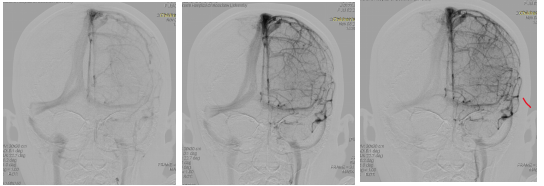

到了8月底,经过一系列治疗,虽然眼压正常,但双眼仍有乳头水肿。在2020年9月初进行了包括VEP和OCT在内的一系列眼科检查,同期未见明显的临床好转。9月11日至17日又对妮妮进行了头部核磁共振检查,发现双侧视神经走行迂曲,双侧乙状窦变薄。同时影像学表现脑室小。

目前可以考虑的可能原因是MRI血管图像显示的乙状窦狭窄

这些狭窄会阻碍静脉血从颅骨排出,从而增加颅内液体的含量和压力